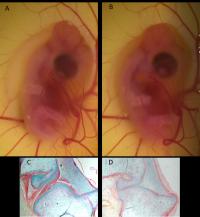

Chick movement in the egg.

video: Chick movement in the egg. It is normal -- and important -- that developing young move in the egg (or womb, in the case of humans). view more

Credit: Professor Paula Murphy, Trinity College Dublin.